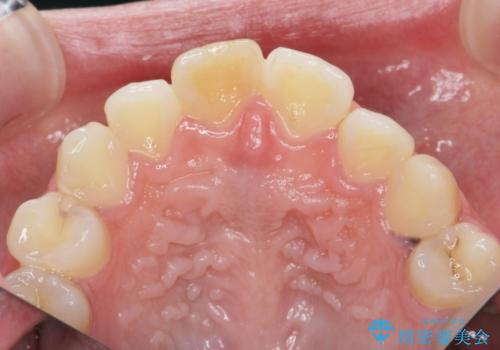

前歯の変色をキレイに セラミッククラウン審美治療

- 前歯の変色が気になる、見た目を改善したい!と審美性の回復を希望され来院されました。

ホワイトニングでは、周囲の歯との色調になじむほどには白くできないため、ジルコニアセラミッククラウンを用いて審美性を回復します。

周囲の歯の色調に調和した審美性の高いセラミッククラウンを製作することができました。